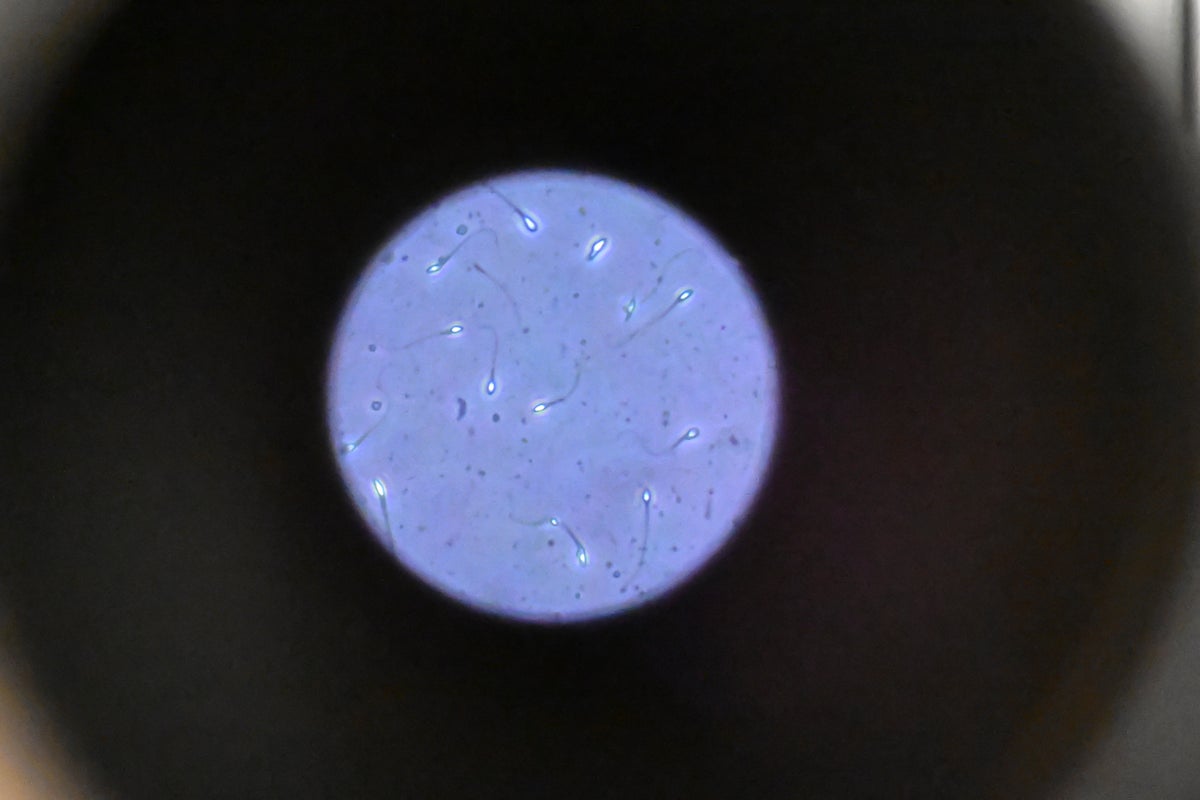

Researchers say lotion is ‘first targeted repair strategy’ for male fertility

© AFP via Getty